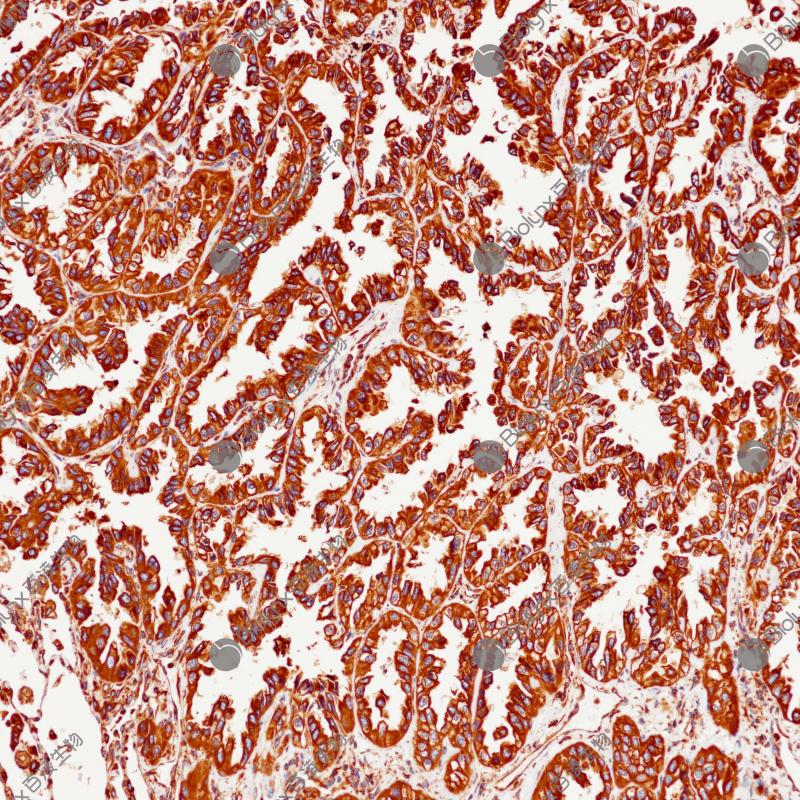

肺腺癌Calreticulin(BP6279)染色

Calreticulin

重组兔单克隆抗体

钙是一种通用的信号分子,参与许多细胞功能,如细胞运动、代谢、蛋白质修饰等。钙储存在内质网(ER)中,由钙结合伴侣如钙联蛋白和钙网蛋白(Calreticulin)缓冲。Calreticulin还可以作为内质网伴侣,确保新合成的糖蛋白的适当折叠和质量控制。钙网蛋白在各种正常组织和肿瘤组织中均有表达。研究表明,钙网蛋白能够刺激机体的抗肿瘤免疫反应,常用于肿瘤免疫相关的研究。

阳性对照

肺腺癌

亚细胞定位

细胞质